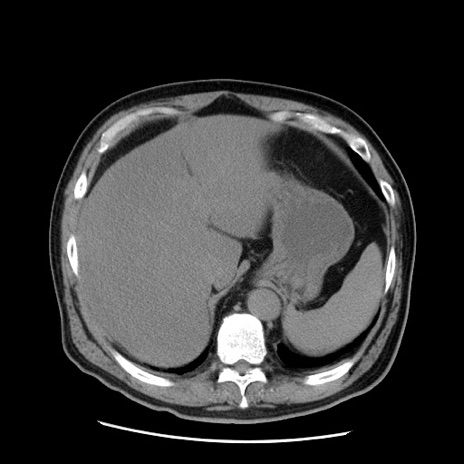

症例20(横断像)

【症例】 60歳代男性

【主訴】 腹部膨満、嘔吐

【現病歴】5日前頃より倦怠感を認め食事量減少し4日前の朝嘔吐、食事摂取困難となった。 3日前近医受診し点滴施行され整腸剤などを処方された。 当日他院を受診し、腹部膨満著明、炎症反応の上昇(CRP10.8、WBC11200)あり、紹介受診となる。

【身体所見】 意識JCS1 受け答えがはっきりしないBP 111/57mHg、 P 67bpm、、BT35.2°C、SpO2 97%(RA)、 腹部:膨隆、打診で鼓音あり、全体的に圧痛有り、腸蠕動音(-)、反跳痛ははっきりせず。

【データ】WBC 11400、CRP 14.20